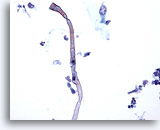

Lavado bronquial

Las hifas de Candida sp pueden representar contaminación oral de la muestra o una neumonía fúngica subyacente. 40x

Lavado bronquial

Las hifas de Candida sp pueden representar contaminación oral de la muestra o una neumonía fúngica subyacente.

40x